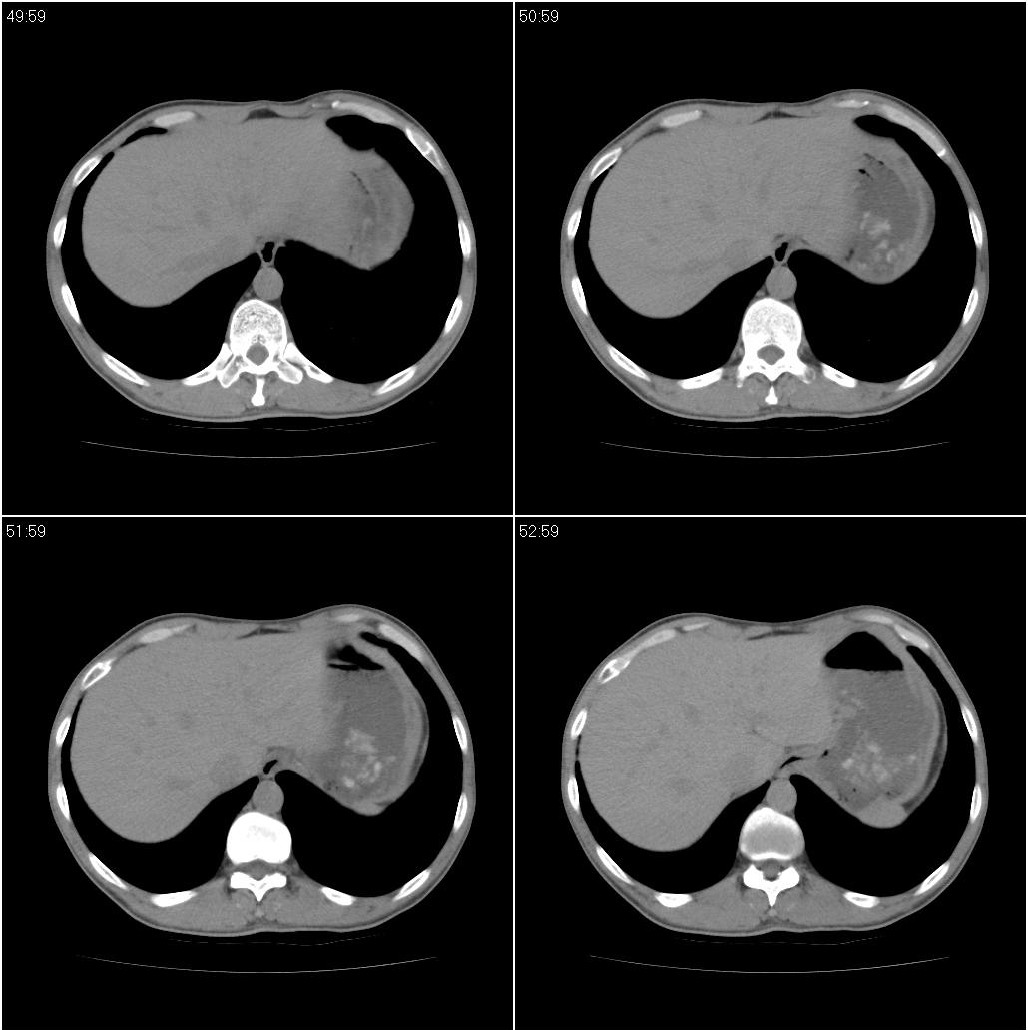

标题: CT23980:男性,47岁。近来咳痰、咳血,血沉增快(40左右),

男性,47岁。近来咳痰、咳血,血沉增快(40左右),痰中未检出结核杆菌。

两肺继发性肺结核并多发性结核球形成,部分病灶内空洞形成。

符合继发性结核表现部分空洞形成并播散